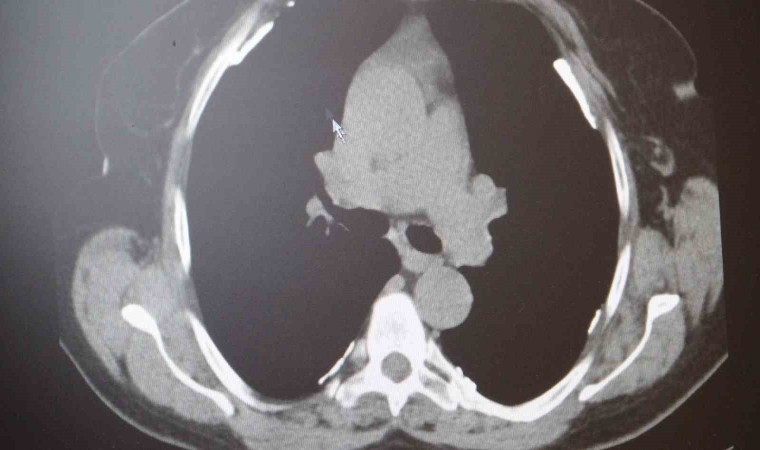

Prof. Dr. Sait Karakurt, "Biliyorsunuz savaş bölgeleri yıkım olan bölgeler. Binaların yıkımı ile birlikte oluşan toz ve parçacıklarla insanlar karşı karşıya kalıyor. bunlar da vücuda zarar verebilir. Bu tozlar içerisinde bir de asbest var. Asbest dikiş iğnesi gibi sivri bir maddedir. Nefes yoluyla akciğere çekildiği zaman adeta oraya batıyor ve vücut bunu uzaklaştıramıyor. Asbeste maruz kalanların 5 kat daha fazla akciğer kanserine yakalandığını biliyoruz. Savaş bölgesinde bulunanlar için mutlaka bulabiliyorsa N95 veya N99 maske takmaları gerekir. Ve yine bölgede patlamalar sonucu oluşan şok dalgaları insan vücudundan geçerken enerjiye bağlı olarak vücuda zarar veriyor. Akciğerde kanama, yırtılma ve ödem meydana getirebiliyor. Bu da zamanla solunum yetmezliğine giden problemler oluşturabiliyor. O bölgelerde yangın da fazla oluyor. yanmaya bağlı partikül ve parçacıklar akciğerlere girip en uç noktasına kadar ulaşıp oradan da vücuda geçme ihtimali olabiliyor. Yangın sırasında dumana maruz kalmak da sorun oluşturuyor. Bir başka sorun da hastalarda var olan hastalıkların artmasıdır. Örneğin astım hastasının yangınlar sonrası karşılaştığı duman ve tozlardan sonra hastalığı alevlenebilir veya çok ciddi boyutlara ulaşabilir. Ya da hiç astımı olmayan bir kişinin aileden gelen astım genetiği vardır, bu yoğun mağduriyet sonrası ilk defa kendisini orada gösterebilir. Patlayıcılar içerisinde bulunan bir takım kimyasallar vücuda zarar verebilir. Fosfor atmosfere girdiği zaman su buharı ile birleşip fosforik asit haline dönebilir. Bu ağırdır ve aşağıya doğru çöker. Yeryüzünde çukur gibi yerlerde daha çok gözükebilir. Deriye temas etmesi halinde yaralar meydana getirir. Nefes yoluyla akciğere çekilmesi aynı yaraların akciğerde de oluşmasına sebebiyet verir. Korunma yöntemi olarak yapacak çok bir şey yok fakat maske takılabilir" dedi.